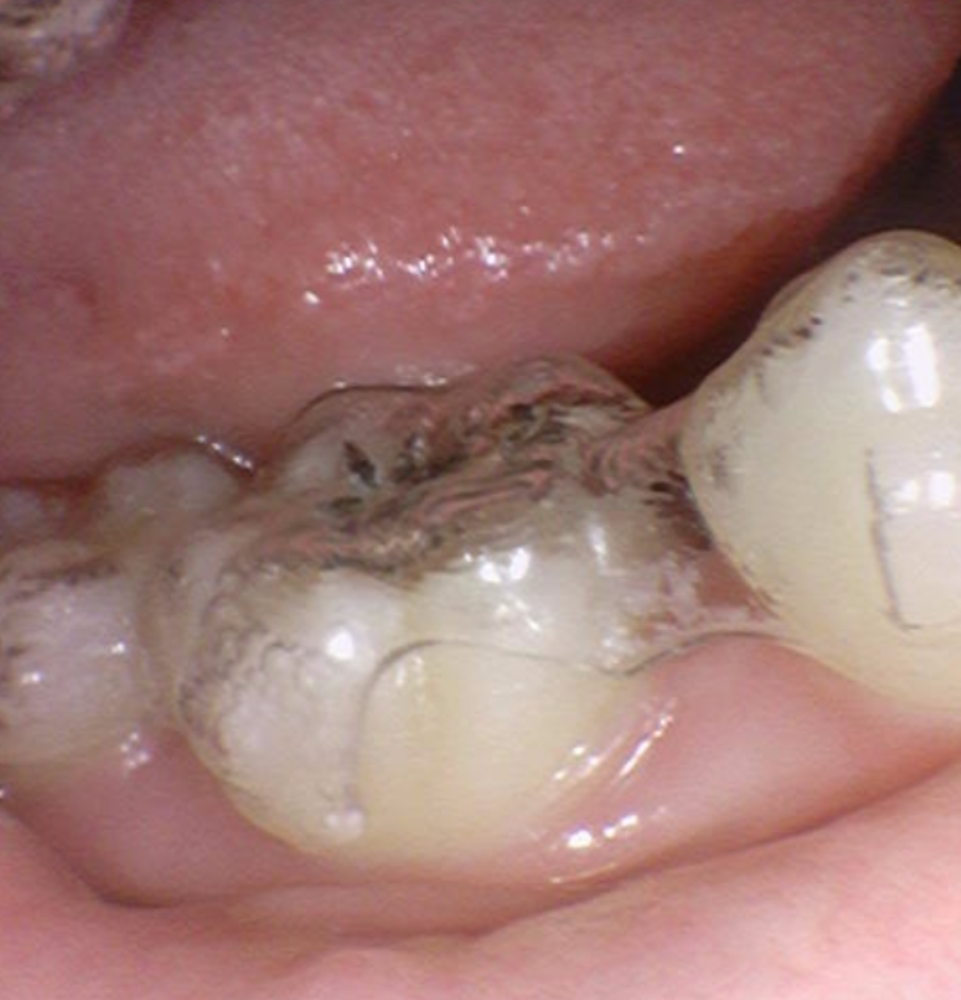

250623 치아 사이 공간을 투명교정으로 줄이는 모습